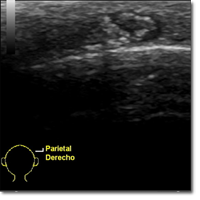

Niño de 7 años que acude a consulta de Atención Primaria por aparición de tumoración cervical de...

Álvarez García J, Sáez López E, Mateos Torre P.

23 septiembre 2025